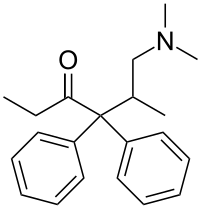

Amidones

Structures

| Amidones | ||||